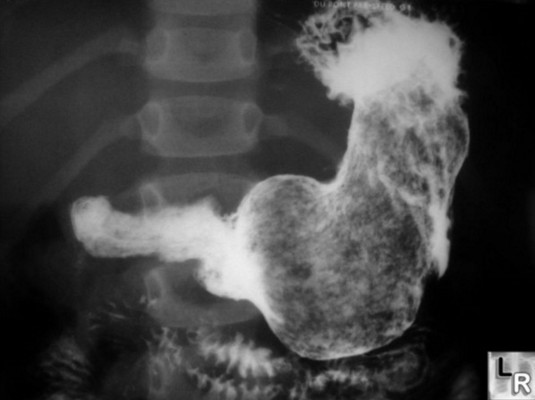

Для выполнения рентгеновского исследования желудка и пищевода пациенту необходимо выпить небольшое количество суспензии сульфата бария. Эта жидкость безопасна для здоровья в указанных объемах и представляет собой густую белую массу с молочным оттенком и легким меловым привкусом. В случае, если у пациента наблюдается индивидуальная непереносимость сульфатов или солей бария, в качестве контрастного вещества могут быть использованы йодиды.

После того как пациент сделает несколько глотков сульфата бария, врач может предложить выпить шипучий раствор или таблетки Аэрон для повышения контрастности. Также может быть использовано зондирование для введения газа в желудок, что помогает уменьшить его складчатость и выровнять слизистую оболочку. После этой процедуры пациенту снова потребуется сделать несколько глотков сульфата бария.

Прием бария позволяет визуализировать стенки желудка, оценить его перистальтическую активность в вертикальном положении и определить расположение органа в брюшной полости. Исследование желудка осуществляется с помощью монитора, и по мере продвижения бариевой соли в желудок делается серия снимков, которые показывают состояние пищевода и поверхности желудка. Эти снимки анализируются позже, на основании чего формируется заключение. На изображениях могут появляться тени, которые играют важную роль в интерпретации результатов. Во время съемки пациента просят задержать дыхание для повышения качества изображений и точности результатов.

Процедура заполнения желудка контрастными веществами и сканирования органов обычно занимает не более 25-30 минут, однако иногда она может затянуться. Исследование начинается с того, что пациент принимает вертикальное положение, и желудок просвечивается с левой стороны. Вторая часть исследования проводится в лежачем положении на специальном рентгеновском столе, где желудок сканируется в горизонтальной плоскости. Для равномерного распределения контрастной жидкости по стенкам желудка врач периодически пальпирует область живота.